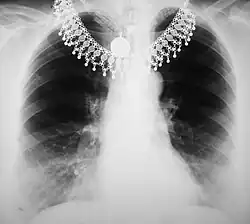

The overall effect of tissue attenuation is illustrated in the Figure 3.9 for the case of a chest radiograph. The exposed area of the patient consists in simplistic terms of air, tissues and bone and is surrounded by the rectangular collimator leaves. The air provides relatively negligible attenuation, while the bone provides substantial attenuation - and tissues provide an intermediate amount. As a result, bone can generate relatively high attenuation at lower X-ray energies and their X-rays shadows can interfere with the visualisation of the lung fields. Increasing the X-ray energy, by increasing the kV, will increase bone penetrability and reduce their shadowing effect. The overall result is a change in the prominence of features associated with different regions in the image histogram.

A typical image is shown in Figure 3.10. It can be seen that bone has a brighter shade of grey than that of the enveloping tissue and is brighter still than the surrounding air. This is the conventional method of displaying a radiograph such that higher photon attenuation is encoded as a brighter shade of grey.

From our earlier discussion, we can expect bone to absorb X-rays preferentially relative to the surrounding tissue and that the energy of these X-rays should have a strong influence on this absorption difference. It is this difference which generates contrast in radiographic images, and we can therefore expect contrast to reduce with increasing X-ray energy. We can also expect that the influence of scatter should be apparent at all X-rays energies.